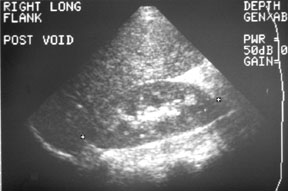

The ultrasound on the right shows a normal right kidney. The left kidney was normal as well.